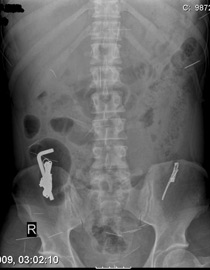

ذهل افراد الطاقم الطبي في قسم الامراض الباطنية، برئاسة د. امجد شلبي، لدى اطلاعهم على صورة الاشعة لمواطن (50 عاما) من حيفا بعد ان تبين لهم انه ابتلع مجموعة اجسام بدت غريبة في بطنه وامعائه.

وكان المواطن الحيفاوي قد وصل الى المستشفى وهو يعاني من آلام حادة في بطنه، وقد ابلغ الاطباء بأنه ابتلع اجساما غريبة، ولدى تحويله الى قسم الاشعة "رينتغين" تبين ان بطنه يحتوي على عدد من الاجسام الغربية وقد تحول بطنه الى "صندوق عدة".

من هذا الاجسام مفتاح "هيلين" عود البوظة، غطاء قلم حبر، دبوس شعر، عود تنظيف الاذنين، وقد شكل ابتلاع هذه الاشياء خطرا على حياته، مما اضطر طاقمين طبيين للعمل سوية لاخراج هذه الحاجيات من بطنه واعادتها الى اصحابها!!

وتجدر الاشارة الى ان للمواطن المذكور سوابق في العلاج النفسي، وقد اجريت له عملية مستعجلة عن طريق المريء وصولا الى المعدة والامعاء.